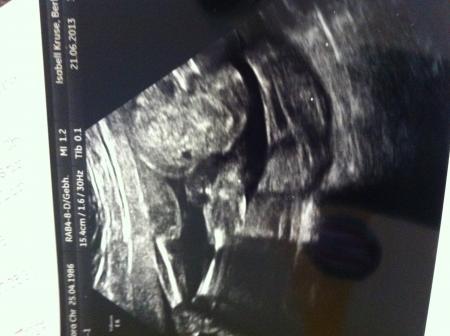

Ich mach mit: nichts 100%iges, aber es sieht nach einem Mädchen aus... Und weil wir schon so viele seitlich-Fotos haben, hier mal von unten:rechts der Po, links die Füßchen

Bild zu